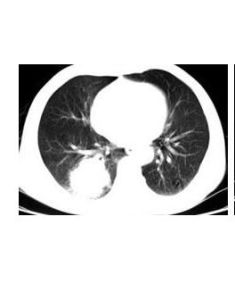

X線表現心影大小正常,但分流量大的肺動靜脈瘺則有心臟擴大。約50%病例在胸片上顯示單個或多個腫塊狀、球狀、結節狀、斑點狀陰影,大小不一,位於1個或多個肺野。病變血管呈繩索樣不透光陰影,從瘺處向肺門延伸,鈣化少見。肋骨侵蝕可因肋間動脈擴大所致,但不常見。透視時病人做Valsalva動作。引起胸內壓增高時,則見動靜脈瘤縮小。定位性診斷依靠心血管造影。

(1)肺內轉移瘤肺動靜脈瘺尤其是多發性的肺動靜脈瘺,其胸部CT顯示肺部有多處的占位病變,極易誤診為肺內轉移瘤,應根據其病歷還有血氣分析等資料進行辨別,尤其要分清楚兩者在CT上的區別。

①胸片上可見一個或多個圓形或卵圓形密度均勻的腫塊,邊界清楚,可有分葉徵象,有時在腫塊的近心端可見兩個條索狀陰影與肺門相連,這就是肺動靜脈瘺的流入和流出血管;